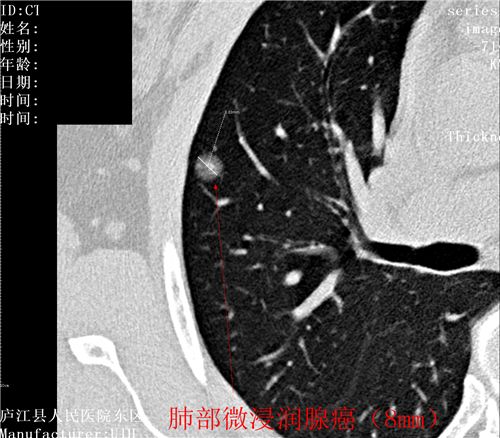

肺癌目前发病率排名第一,肺癌5年生存率任然低于20%,为什么会这么低?就是发现肿瘤时就是晚期肺癌,晚期肺癌无论是手术还是放化疗治疗效果就会差很多。如何能够早期发现?目前国际上达成专家共识,那就是低剂量螺旋CT检查,通俗易懂地说就是接受最小的辐射剂量,达到最好的早期肺癌的诊断效果,要知道,早期肺癌是不痛不痒,没有任何症状的,要想查出它只有CT检查,照张胸片那就意味着是“凶片”。胸部低剂量CT让早期肺癌无处逃遁!

图片展示:健康体检中发现的肿瘤